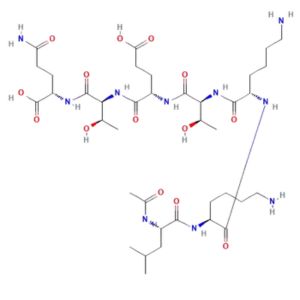

Structure of TB500

Sequence: Ac-Ser-Asp-Lys-Pro-Asp-Met-Ala-Glu-Ile-Glu-Lys-Phe-Asp-Lys-Ser-Lys-Leu-Lys-Lys-Thr-Glu-Thr-Gln-Glu-Lys-Asn-Pro-Leu-Pro-Ser-Lys-Glu-Thr-Ile-Glu-Gln-Glu-Lys-Gln-Ala-Gly-Glu-Ser.

Molecular Formula: C38H68N10O14

Molecular Weight: 4963 g/mol

PubChem CID: 62707662